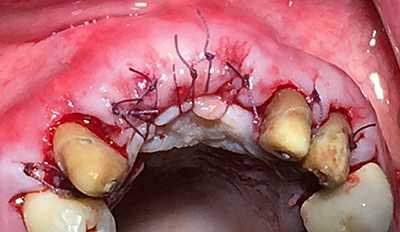

水平切口,鄰牙冠延長。

這時候縫合可能還會存在一些軟組織張力,這時候最好的辦法不是唇側(cè)減張縫合,看我的方法,既可以達到減張的目的又可以保證牙槽嵴頂角化齦充足。

鄰牙重新備牙,制作臨時樹脂橋體,缺牙區(qū)三顆變?yōu)閮深w。下圖是術(shù)后一個月口內(nèi)照。